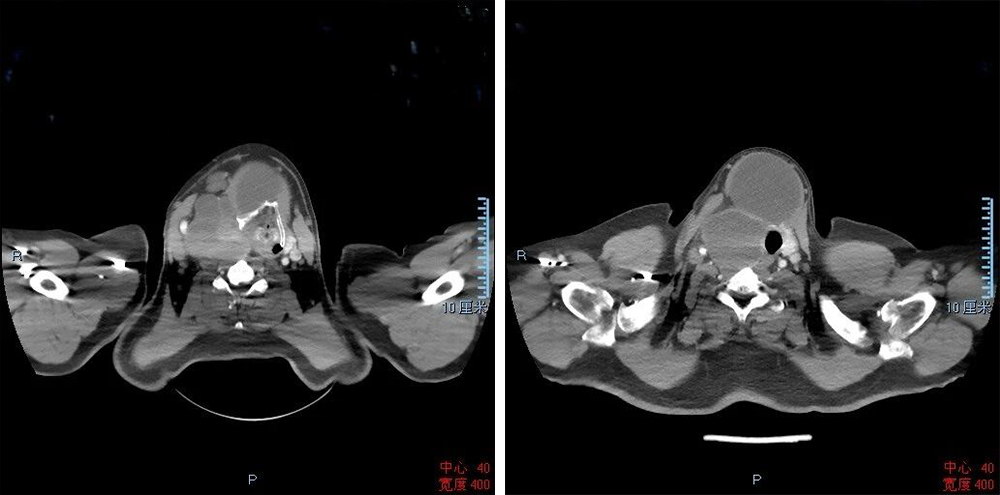

患者因巨大甲状腺恶性肿瘤入院,肿瘤体积达15×15厘米,长期重度压迫咽喉腔,致口咽上移、喉与气管严重偏移、气道显著狭窄,局部解剖结构完全畸变,属于极高危困难气道,常规麻醉插管无法实施,仅能采用保留自主呼吸的清醒气管插管。术前虽经深度镇静、充分表面麻醉等周密准备,术中可视喉镜与纤维支气管镜仍无法清晰显露声门,插管陷入绝境。危急时刻,患者血氧饱和度持续下降,生命通道亟待建立。杨静远主任凭借数十年临床积淀与精湛技艺,沉着实施困难气道盲插技术,一次操作精准到位,迅速搭建生命通路,为手术实施筑牢安全屏障。

麻醉险关攻克后,头颈外科团队正式启动手术。术中探查证实,患者病情远超术前评估:肿瘤体积巨大、侵袭性极强,已侵犯气管壁、食管壁,局部组织重度粘连、解剖层次完全紊乱,周边毗邻喉返神经、颈部大血管等关键结构,分离切除风险极高、操作难度极大。团队秉持精准、微创、安全的手术理念,沉着应战、精细操作,全程严密保护神经与血管功能,有序分离粘连组织,妥善修复受侵气管与食管,最终实现肿瘤完整根治性切除。手术全程患者生命体征平稳,高难度、高风险极限手术圆满收官。